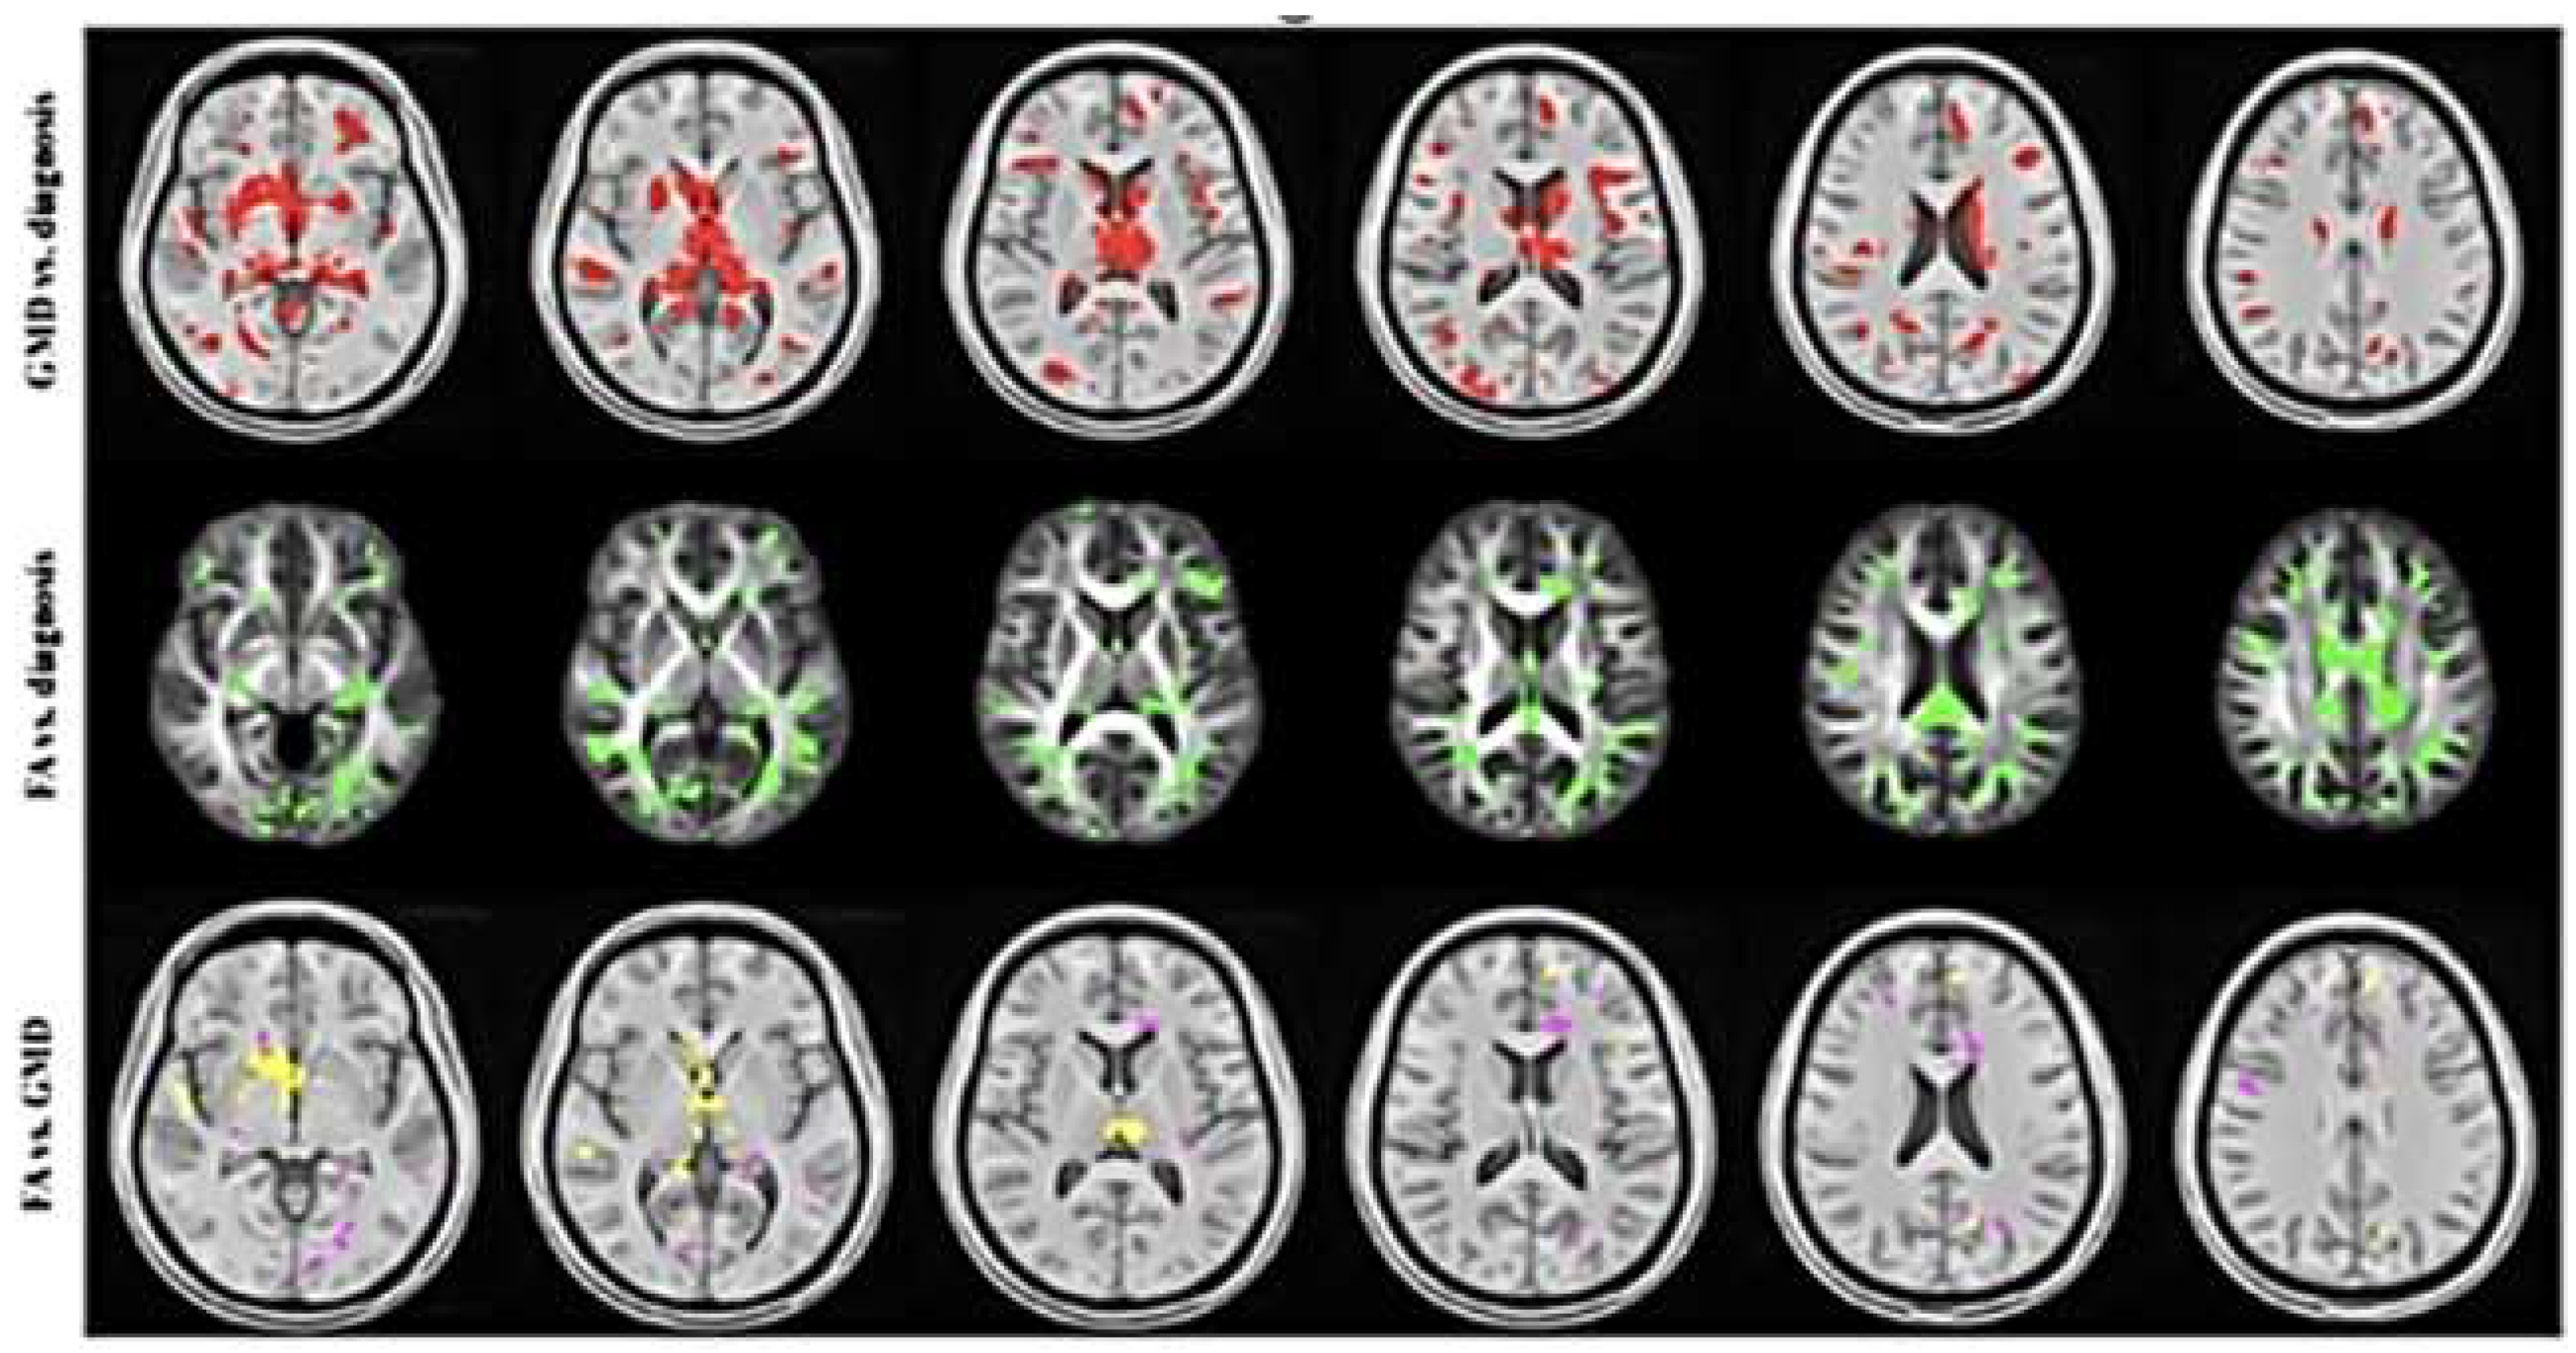

- Wooten, D.W.; Ortiz-Terán, L.; Zubcevik, N.; Zhang, X.; Huang, C.; Sepulcre, J.; Atassi, N.; Johnson, K.A.; Zafonte, R.D.; El Fakhri, G. Multi-Modal Signatures of Tau Pathology, Neuronal Fiber Integrity, and Functional Connectivity in Traumatic Brain Injury. J. Neurotrauma 2019, 36, 3233–3243. [Google Scholar] [CrossRef]